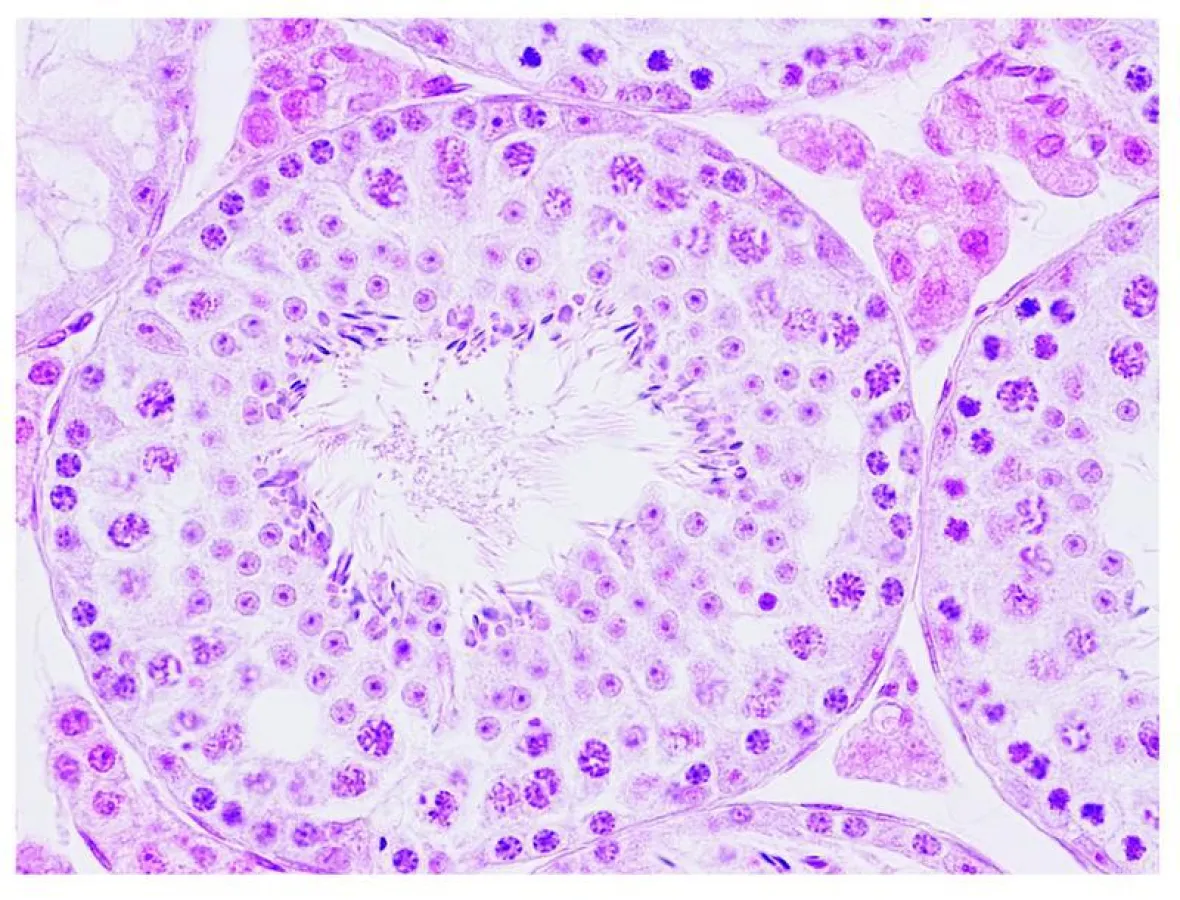

Worldwide approximately nine percent of women and men are involuntarily childless. In 40 to 50 percent of the cases this is due to male infertility. This infertility can be caused by different reasons, one of them are mutations in the mitochondrial DNA. Mitochondria are tiny energy factories inside the cell and harbor their own independent genome – the mitochondrial DNA (mtDNA). Mice suffering from a high number of mutations in the mtDNA are infertile and have fewer and less motile sperm.

Max Planck scientist Min Jiang and her colleagues studied these mice and found a way to overcome the consequences of these mutations. ”We increased the total amount of mtDNA in the mitochondria of the testis. This did not change the proportion of mtDNA with mutations, but it increased the absolute number of non-mutated mtDNA, which restored mitochondrial energy production and semen quality”, explains Jiang.